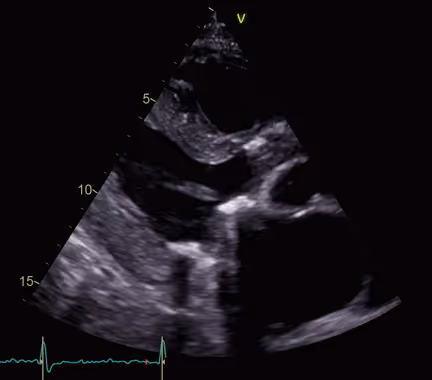

Patient with a Stanford type A aortic dissection

2021-03-08

in

Clinical Cases